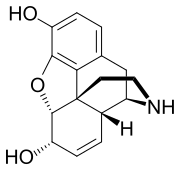

Desomorphine Desomorphine (Dihydrodesoxymorphine) |

Dihydromorphine Dihydromorphine |